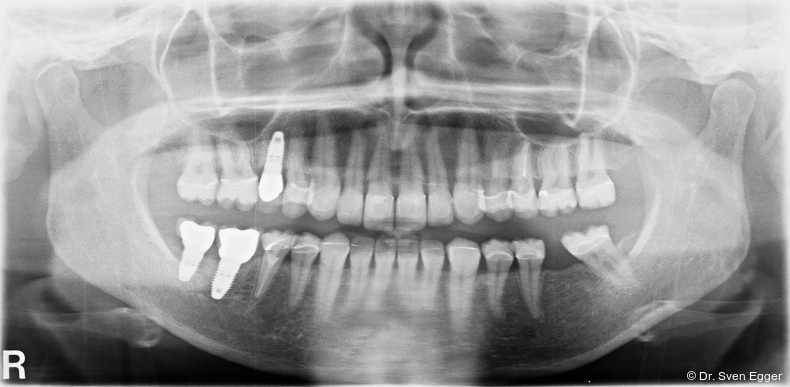

Das OPG zeigt insuffiziente endodontische Versorgungen an 15, 25 und 46. Die Kieferhöhle rechts zeigt eine kirschgroße, kugelige Verschattung (Überweisung/Abklärung Kieferchirurgie).

Die Follow-up-Untersuchung zeigte ein Ergebnis, mit dem die Patientin nach 15 Jahren Tragezeit weiterhin vollumfänglich zufrieden ist. Die keramische Teilkrone an Zahn 17 wurde am 31.5.2022 aufgrund Debondings nach erneuter Konditionierung wieder eingesetzt. Die Kieferhöhlen sind verschattungsfrei und zeigen keine Anzeichen eines Rezidivs der in 2007 erfolgten Zystenoperation in der rechten Kieferhöhle (Mukozele). Die endodontisch revidierten Zähne 25 und 45 zeigen weder klinisch noch röntgenologisch Auffälligkeiten. Die Stellung der Ober- und Unterkieferfront sowie die in ZKP etablierte horizontale und vertikale Relation des Unterkiefers ist stabil und bereitet keinerlei Schwierigkeiten. Die Implantate weisen klinisch und röntgenologisch schöne Hart- und Weichgewebsverhältnisse auf. Die häusliche Mundhygiene ist sehr gut. Es sind keine Anzeichen einer Funktionsproblematik zu erkennen. Die Michigan-Schiene wurde 2022 erneuert. Für die vorliegende Situation lässt sich damit auch weiterhin eine sehr gute Langzeitprognose aussprechen (Abb. 18–25).